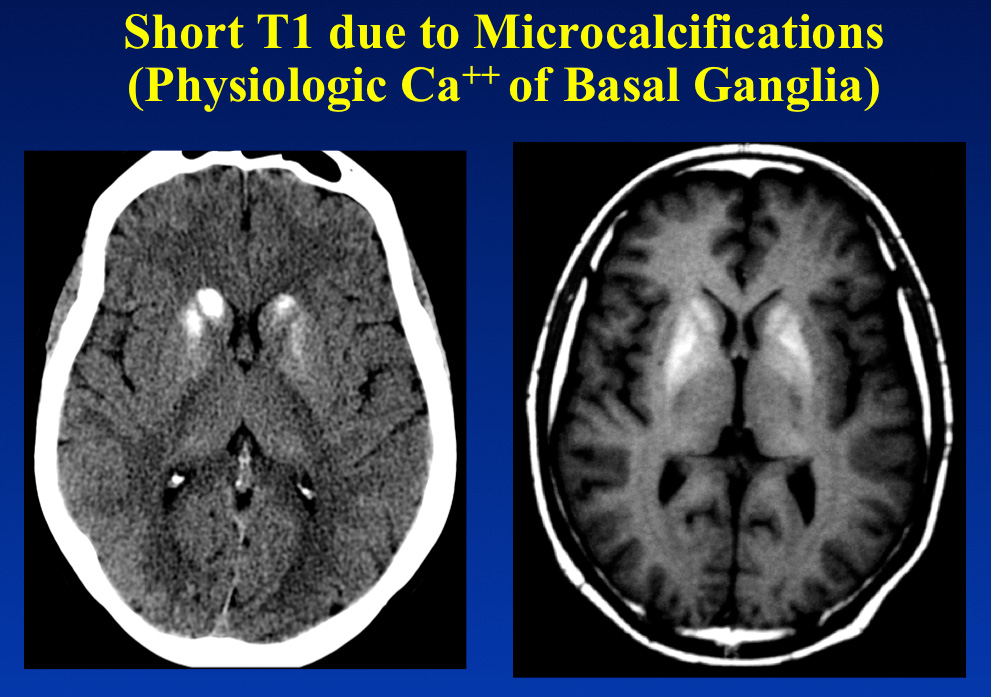

Fazekas grades. Церебральная микроангиопатия кт. Церебральная микроангиопатия головного мозга кт. Микроангиопатии головного мозга что это такое.

Fazekas grades. Церебральная микроангиопатия кт. Церебральная микроангиопатия головного мозга кт. Микроангиопатии головного мозга что это такое.